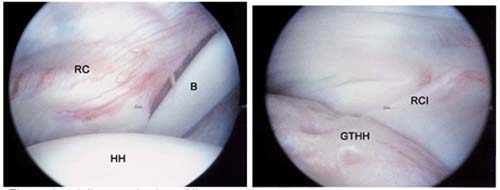

Left, Arthroscopic view of the rotator cuff from within the joint shows the rotator cuff (RC),

the head of the humerus (HH), and the biceps tendon (B).